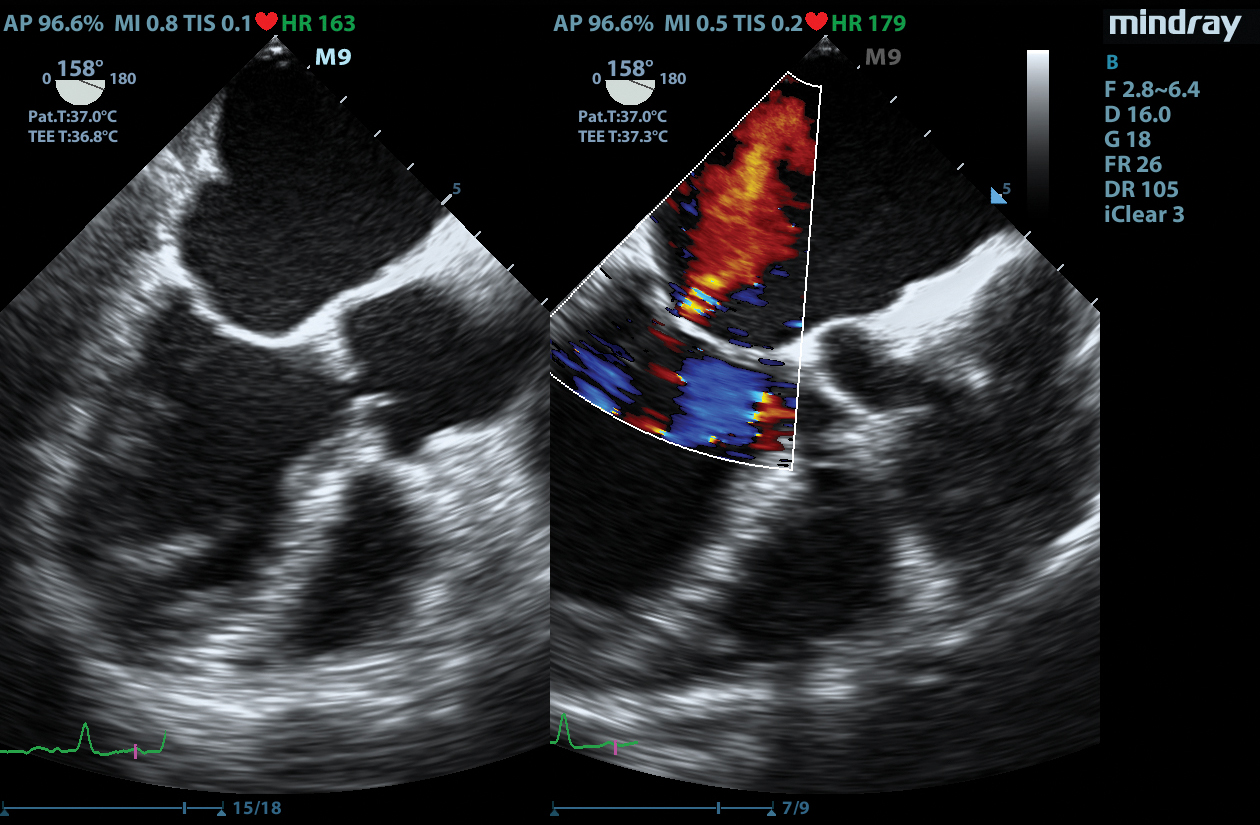

The M9 Ultrasound System Ruby Edition offers a fully-featured, compact ultrasound solution for your most challenging point-of-care exams. Delivering image clarity and advanced capabilities previously only available on larger, cart-based systems, the M9 System defines the new standard for intelligent performance in a mobile, laptop design.

Equipped with single crystal transducers and 3T™ technology for a wide range of exams, the M9 System is a versatile platform for advanced imaging in the vascular lab, emergency departments, critical care environments, and anesthesia practices. The System’s slim profile and ergonomic design allow for effortless flexibility and mobility. Whether it be ultrasound guided procedures at the patient’s bedside or transesophageal echocardiography (TEE) imaging in the critical care unit, this platform can do it all.